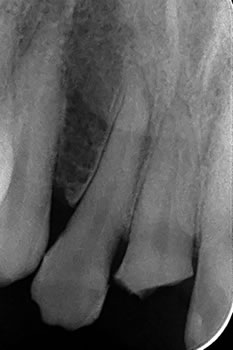

すでに露髄していたので根管治療して、ファイバーコアが装着されてます! |

e.MAX冠は光を透過できる強化ガラスセラミックで審美性に優れています。

いつも依頼している福岡のギコウさんに写真を送って色合わせを頼みましたのでかなり自然な仕上がりになりました!

いつも感謝です! |